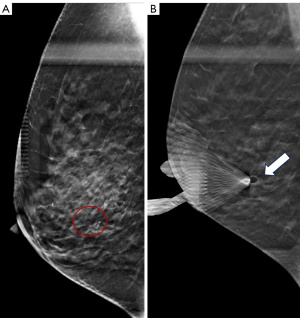

For VABB, after confirming the lesion’s localization, the skin was disinfected, local anesthesia was administered, and a small incision was made. The cutting needle was positioned at the target under DBT guidance, and a 360° cutting motion was employed to collect suspicious calcifications. Subsequent X-ray imaging confirmed the retrieval of calcifications, and DBT imaging verified the excision of the lesion at the biopsy plane (Figure 2).